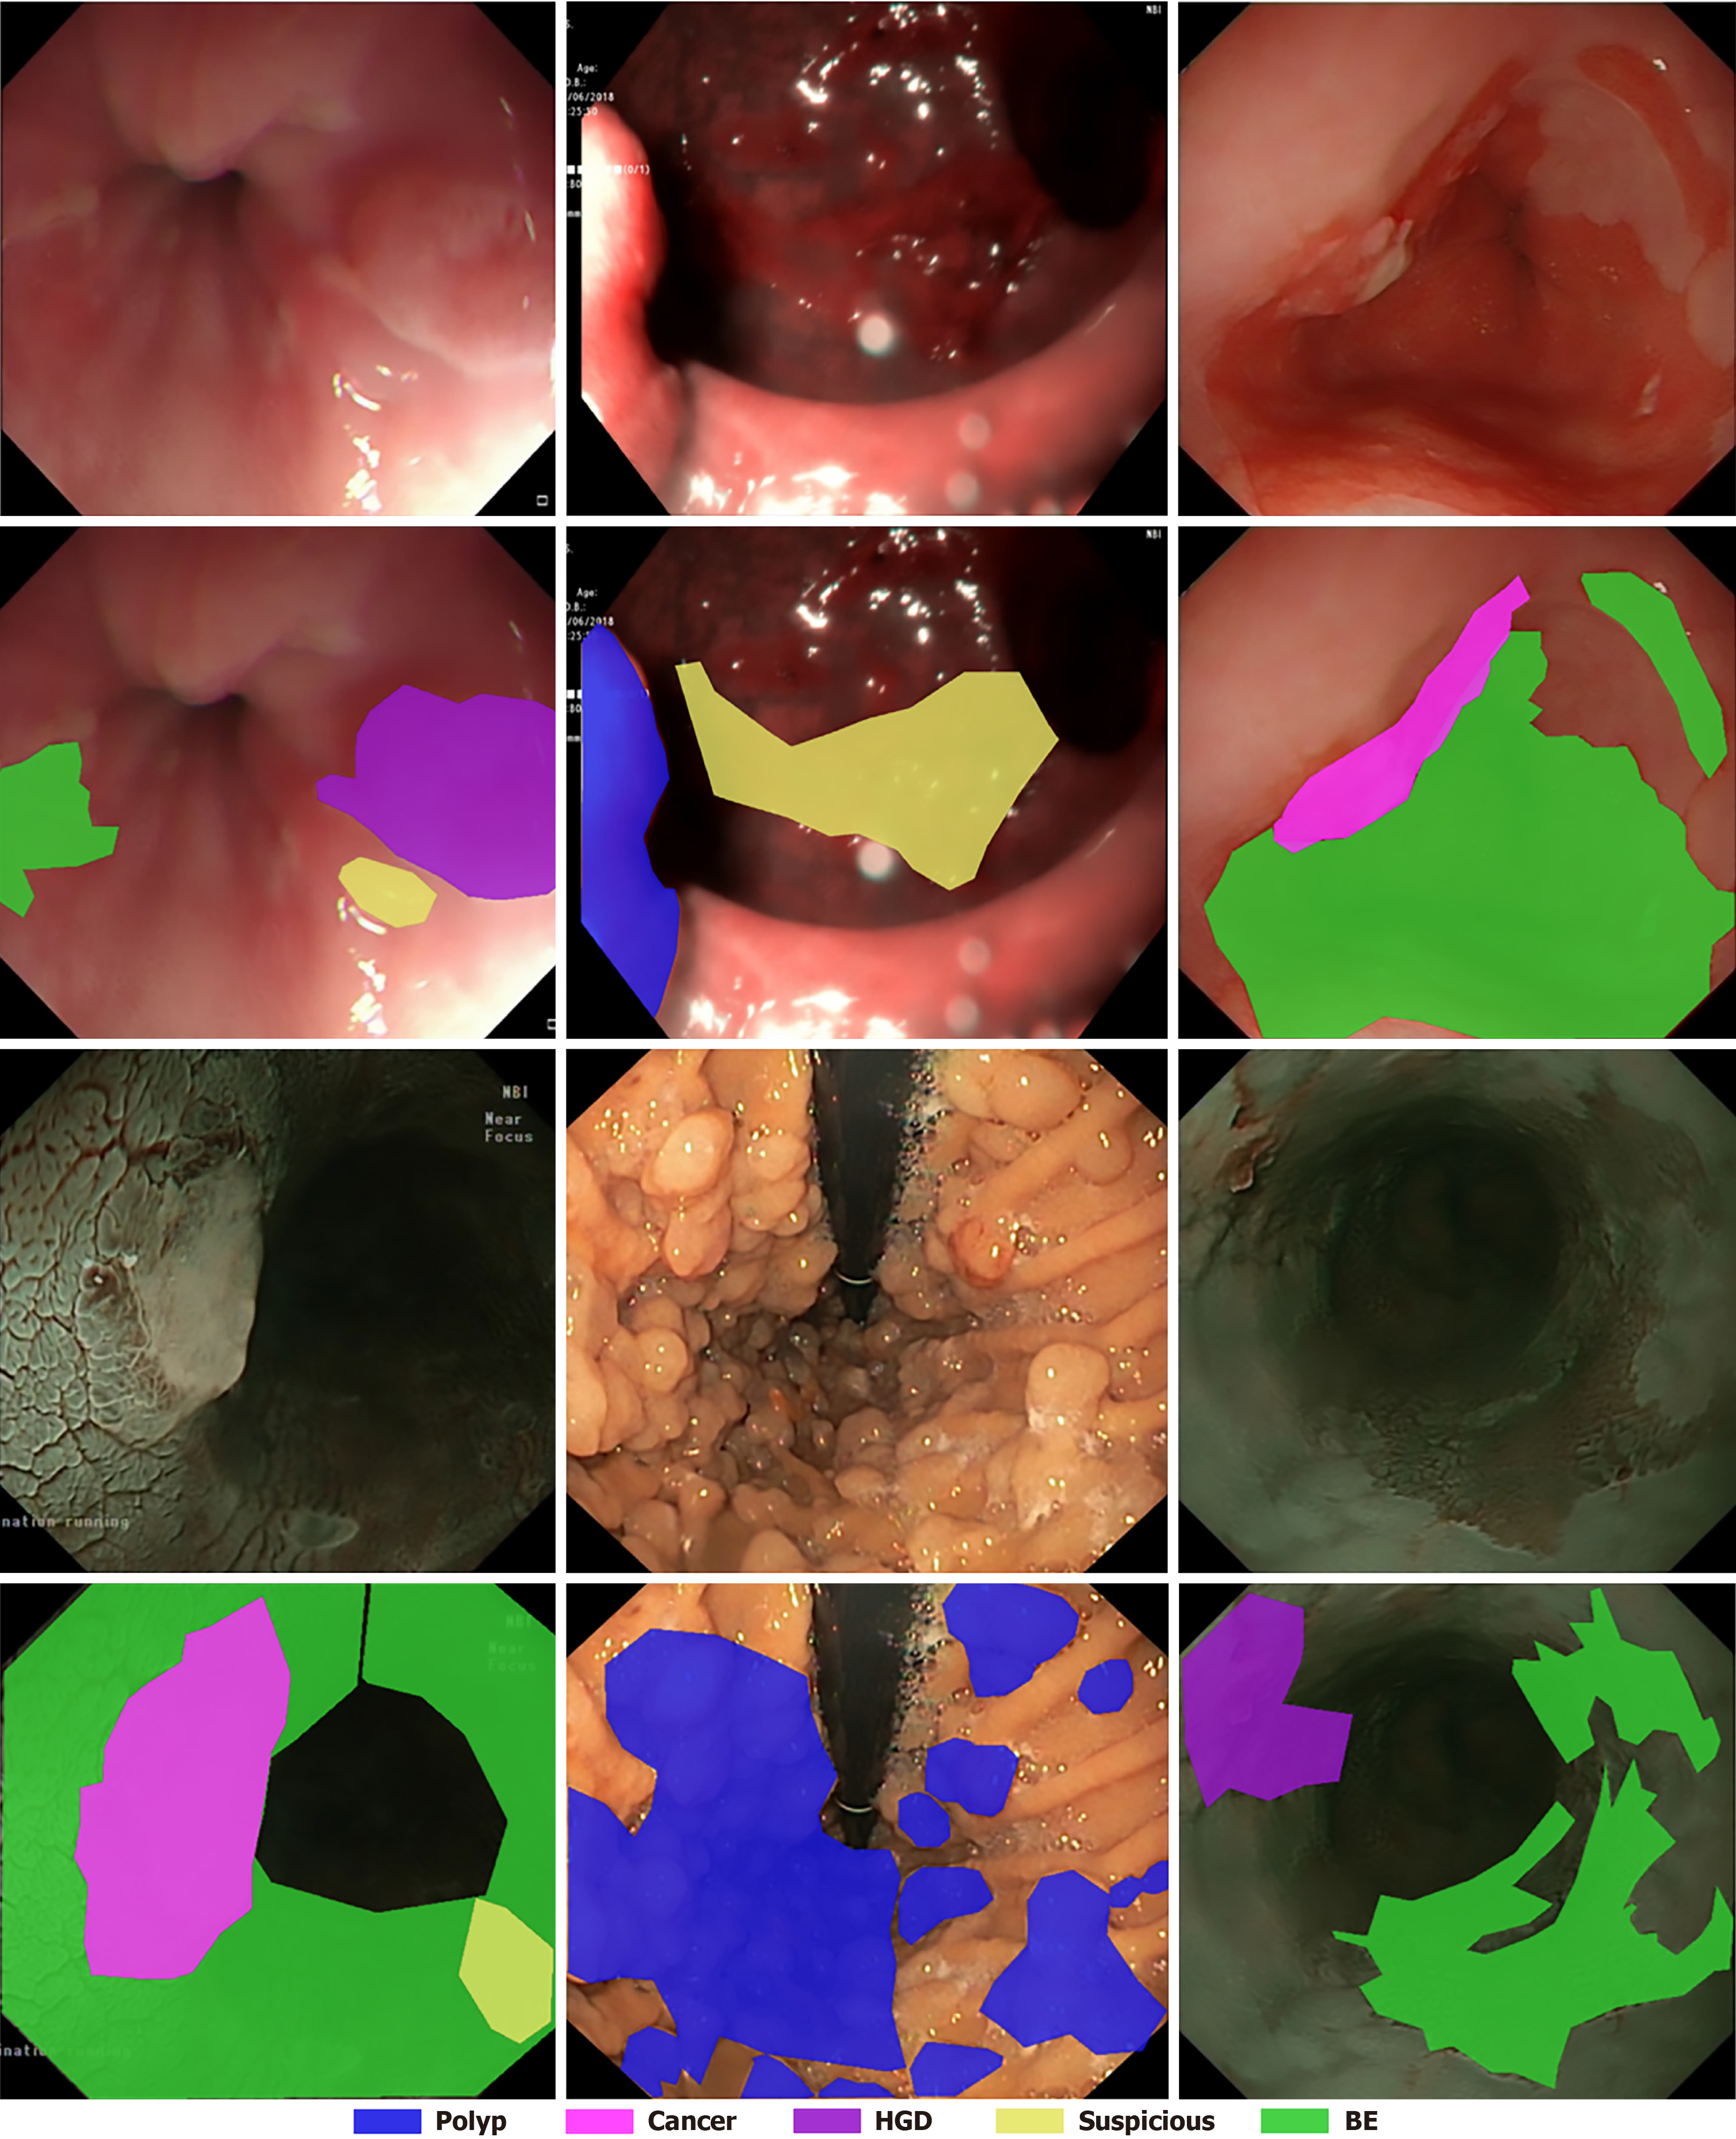

Figure 4 Example images and their masks of the EDD2020 dataset.

HGD: High-grade dysplasia; BE: Barrett’s esophagus.